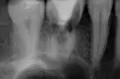

Добрый день. Мне в стоматологии сделали снимок зуба и сказали, что зуб надо удалять, так как вылечить не получится. Подскажите, так ли это? Может стоит обратиться к другим врачам? (фото зуба выслала на e-mail). Зуб № 46. На данный момент зуб не беспокоит. Три месяца назад был флюс, после разреза всё прошло. Антибиотиками не лечила, так как беременность. Сейчас срок 17 недель. Спасибо!

Да, к сожалению зуб необходимо удалить, так как на верхушках всех корней наблюдается обширное воспаление.